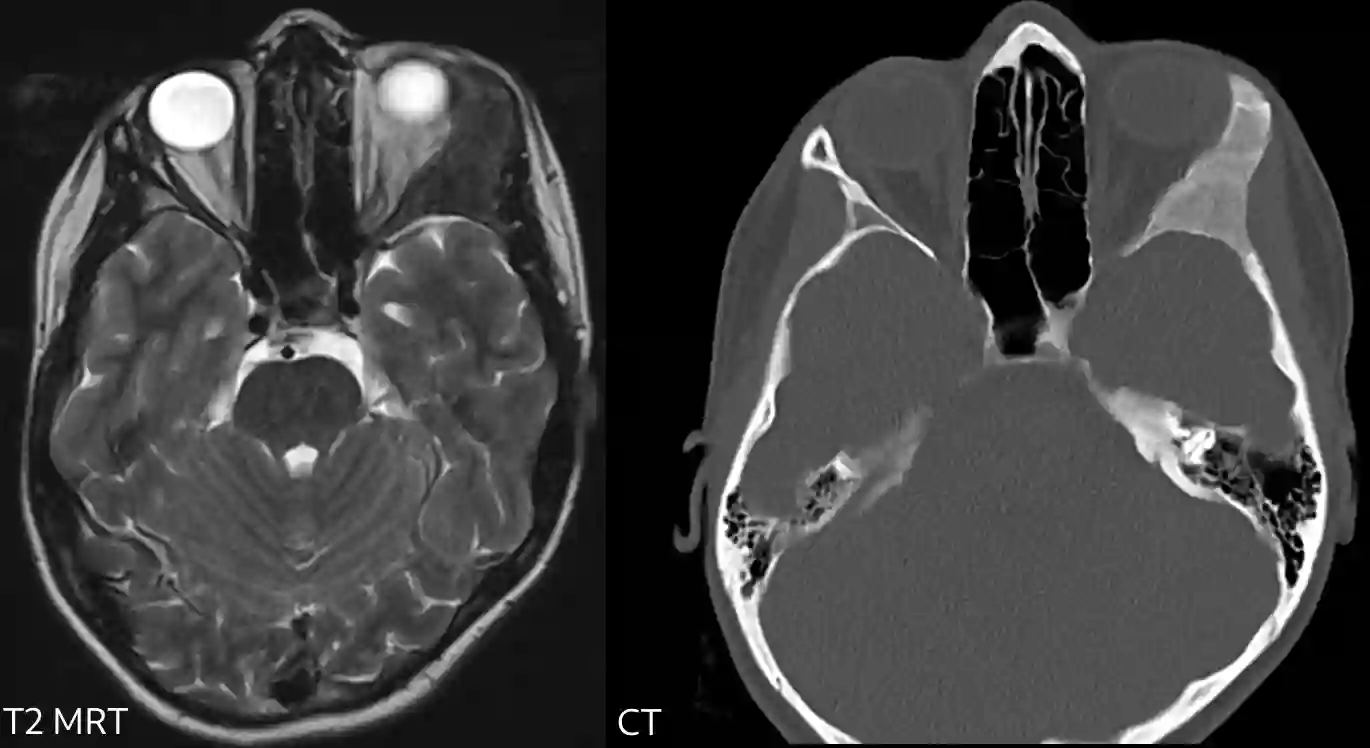

Am Schädel kann man je nach Morphologie drei verschiedene Typen der fibrösen Dysplasie unterscheiden7:

- Zystisch (Wobei hier nicht zystisch im klassischen Sinne gemeint ist): Erweiterung der Diplöe mit Ausdünnung der Tabula externa und wenig Involvierung der Tabula interna. Kommt typischerweise an der Schädelkalotte vor.

- Skletorisch: Betrifft typischerweise die Schädelbasis, insbesondere das Os sphenoidale und die Gesichtsknochen.

- Gemischt: Die Läsion zeigt sich ähnlich dem zystischen Typ mit Anteilen an erhöhter Densität in der Läsion.

Bildgebung

Läsionen einer fibrösen Dysplasie lassen sich im MRT oder in der CT Bildgebung darstellen.